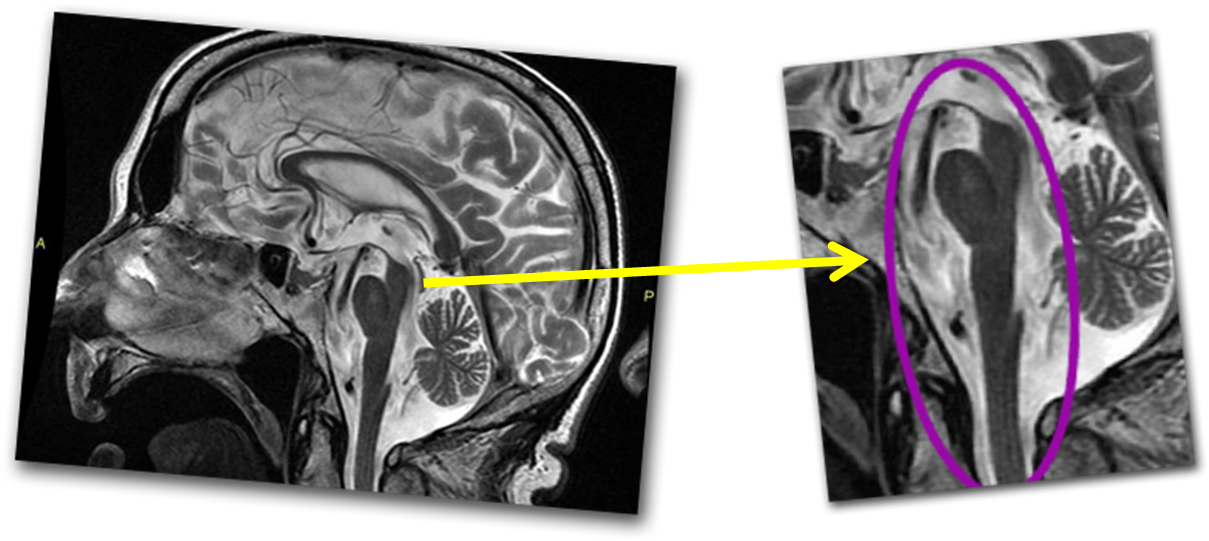

Progressive supranuclear palsy is characterized by decreased cognition, abnormal eye movements (supranuclear vertical gaze palsy), postural instability and falls, as well as Parkinsonian features and speech disturbances 1-3 . It can be divided into a variety of subtypes many of which overlap with other neurodegenerative diseases that share an.. Las complicaciones de la parálisis supranuclear progresiva se deben principalmente a la lentitud y a la dificultad para mover los músculos. Estas complicaciones podrían incluir: Caídas, que pueden provocar lesiones en la cabeza, fracturas y otras lesiones. Dificultad para enfocar los ojos, que también puede causar lesiones.

Key points. Progressive supranuclear palsy (PSP) is very different to Parkinson's disease with readily distinguishable features. PSP is a clinical diagnosis; imaging helps to differentiate mimics. Non-pharmacological management of PSP is as important as pharmacological treatment and should be implemented early.. Diagnóstico. La parálisis supranuclear progresiva puede ser difícil de diagnosticar porque los signos y síntomas son similares a los de la enfermedad de Parkinson. El médico puede sospechar que tienes parálisis supranuclear progresiva en lugar de la enfermedad de Parkinson si sucede lo siguiente: No tienes temblores.